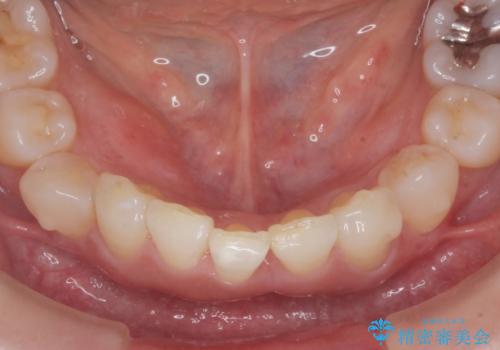

インビザラインで行う前歯のみの部分矯正

- 長年気になっていた前歯の歯並びを改善したいと、矯正治療を希望され思い切って来院されました。

費用と期間を相談し、「気になっているのは前歯だけ。」とのことでしたので前歯のがたつきのみをインビザラインで改善する矯正治療の計画を立てます。

しっかりとマウスピースの装用時間を守っていただき、非常にスムーズに治療を終了することができました。